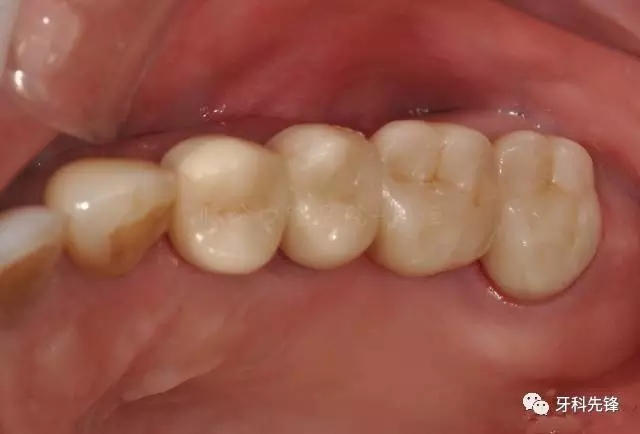

圖29術后頰面照

640.webp (33).jpg

圖30術后頜面照

640.webp (34).jpg